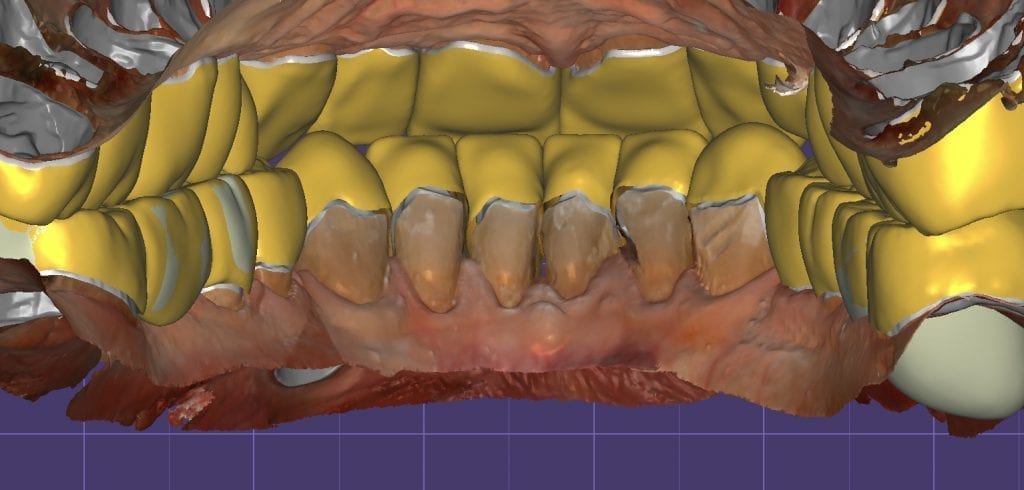

The digital models were then imported into a third party software where a library of tooth morphologies are available for the clinician to choose from.

Once the appropriate library is chosen, the digital wax ups are performed. In the subsequent photos you can see the transparent overlay of the wax-ups to the original position of the existing dentition

Once the case is designed to the ideal vertical dimension then multiple shells can be fabricated for treatment. The wax up model can be uniformly reduced by .5mmm’s circumferentially and a temporary shell can be designed. Once the teeth are prepared, these shells can be relined and seated onto the preps.